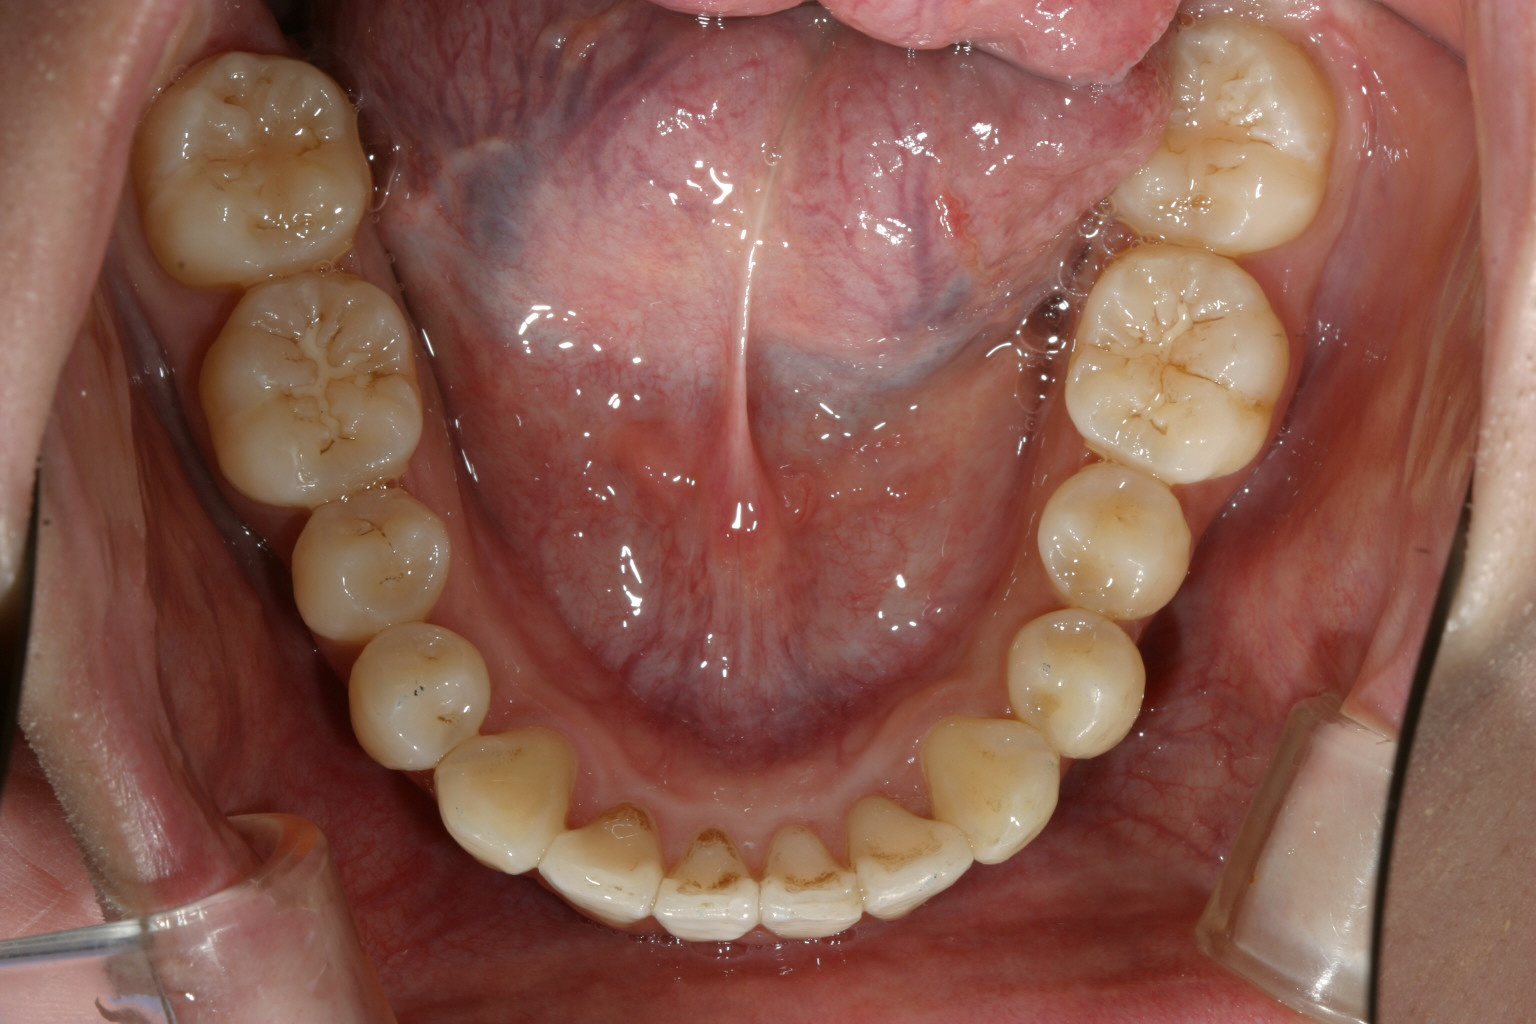

下顎には叢生が目立ちます。

下顎にもリンガルアーチにてアーチ拡大と前歯の叢生治療です。

下顎もリンガルアーチ後インビザラインで治療を行いました。

オーバジェットも綺麗になっています。